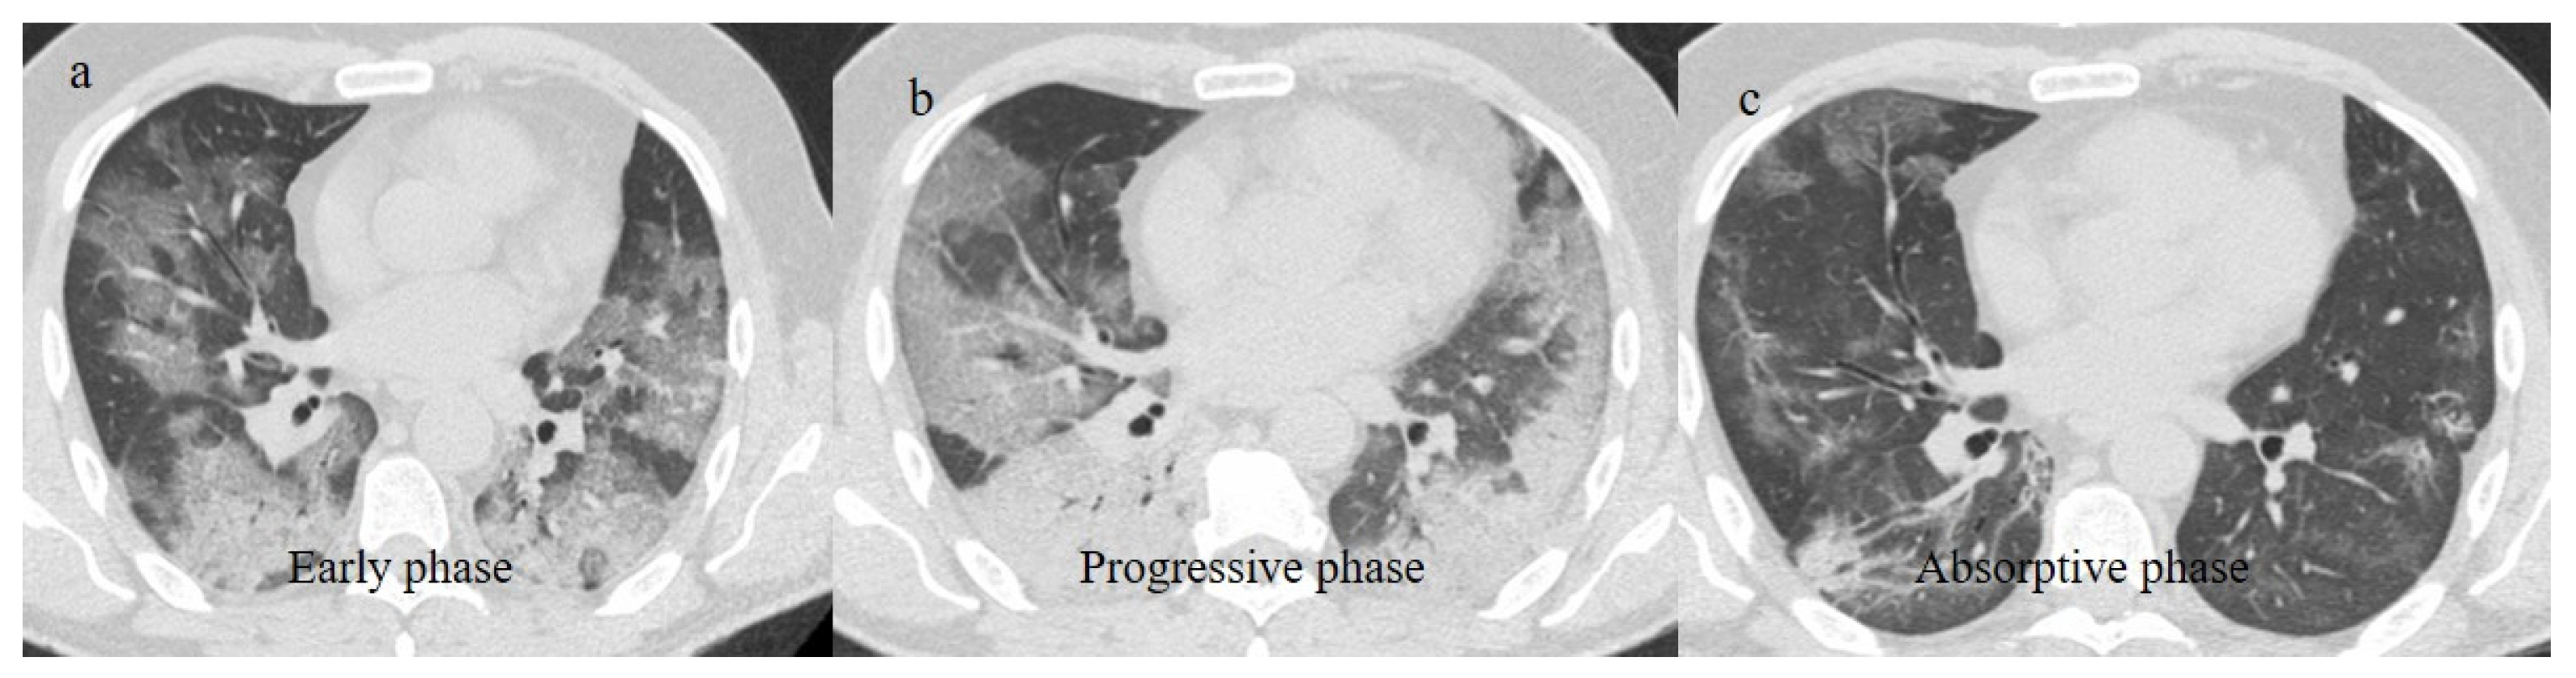

| Typical Appearance | GGOs with a crazy-paving pattern and consolidations in a peripheral and posterior or central-peripheral distribution; multilobar involvement; vascular enlargement, the halo and reversed halo sign; subpleural and parenchymal bands; and architectural distortion. They were predominant since the Delta wave. |

| Typical appearance | From the wild-type to the Delta variant. | Askani et al., 2022 [67] | The Delta variant presented more frequent typical features with more extensive lung involvement than the Omicron variant. The Omicron variant was more frequently associated with the absence of pneumonia. |

| Inui et al., 2021 [68] | Typical findings were characteristic of the wild type to the Delta variant. GGOs with consolidation and repair changes were more frequent in the Delta variant. The Delta variant also showed more rapid pneumonia progression than the wild-type and Alpha variants. | ||

| Typical findings of interstitial pneumonia with peripheral or peripheral central distribution from the wild/type variant since Delta variant |

| Absence of pneumonia or atypical findings during the Omicron wave | |||